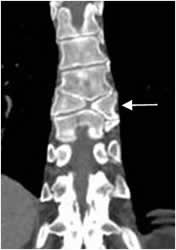

Fig 15. TBC.

A: Rx AP y B: RM sagital en T2. Leve desviación derecha y cifosis dorsolumbar, como secuela de infección por TBC.